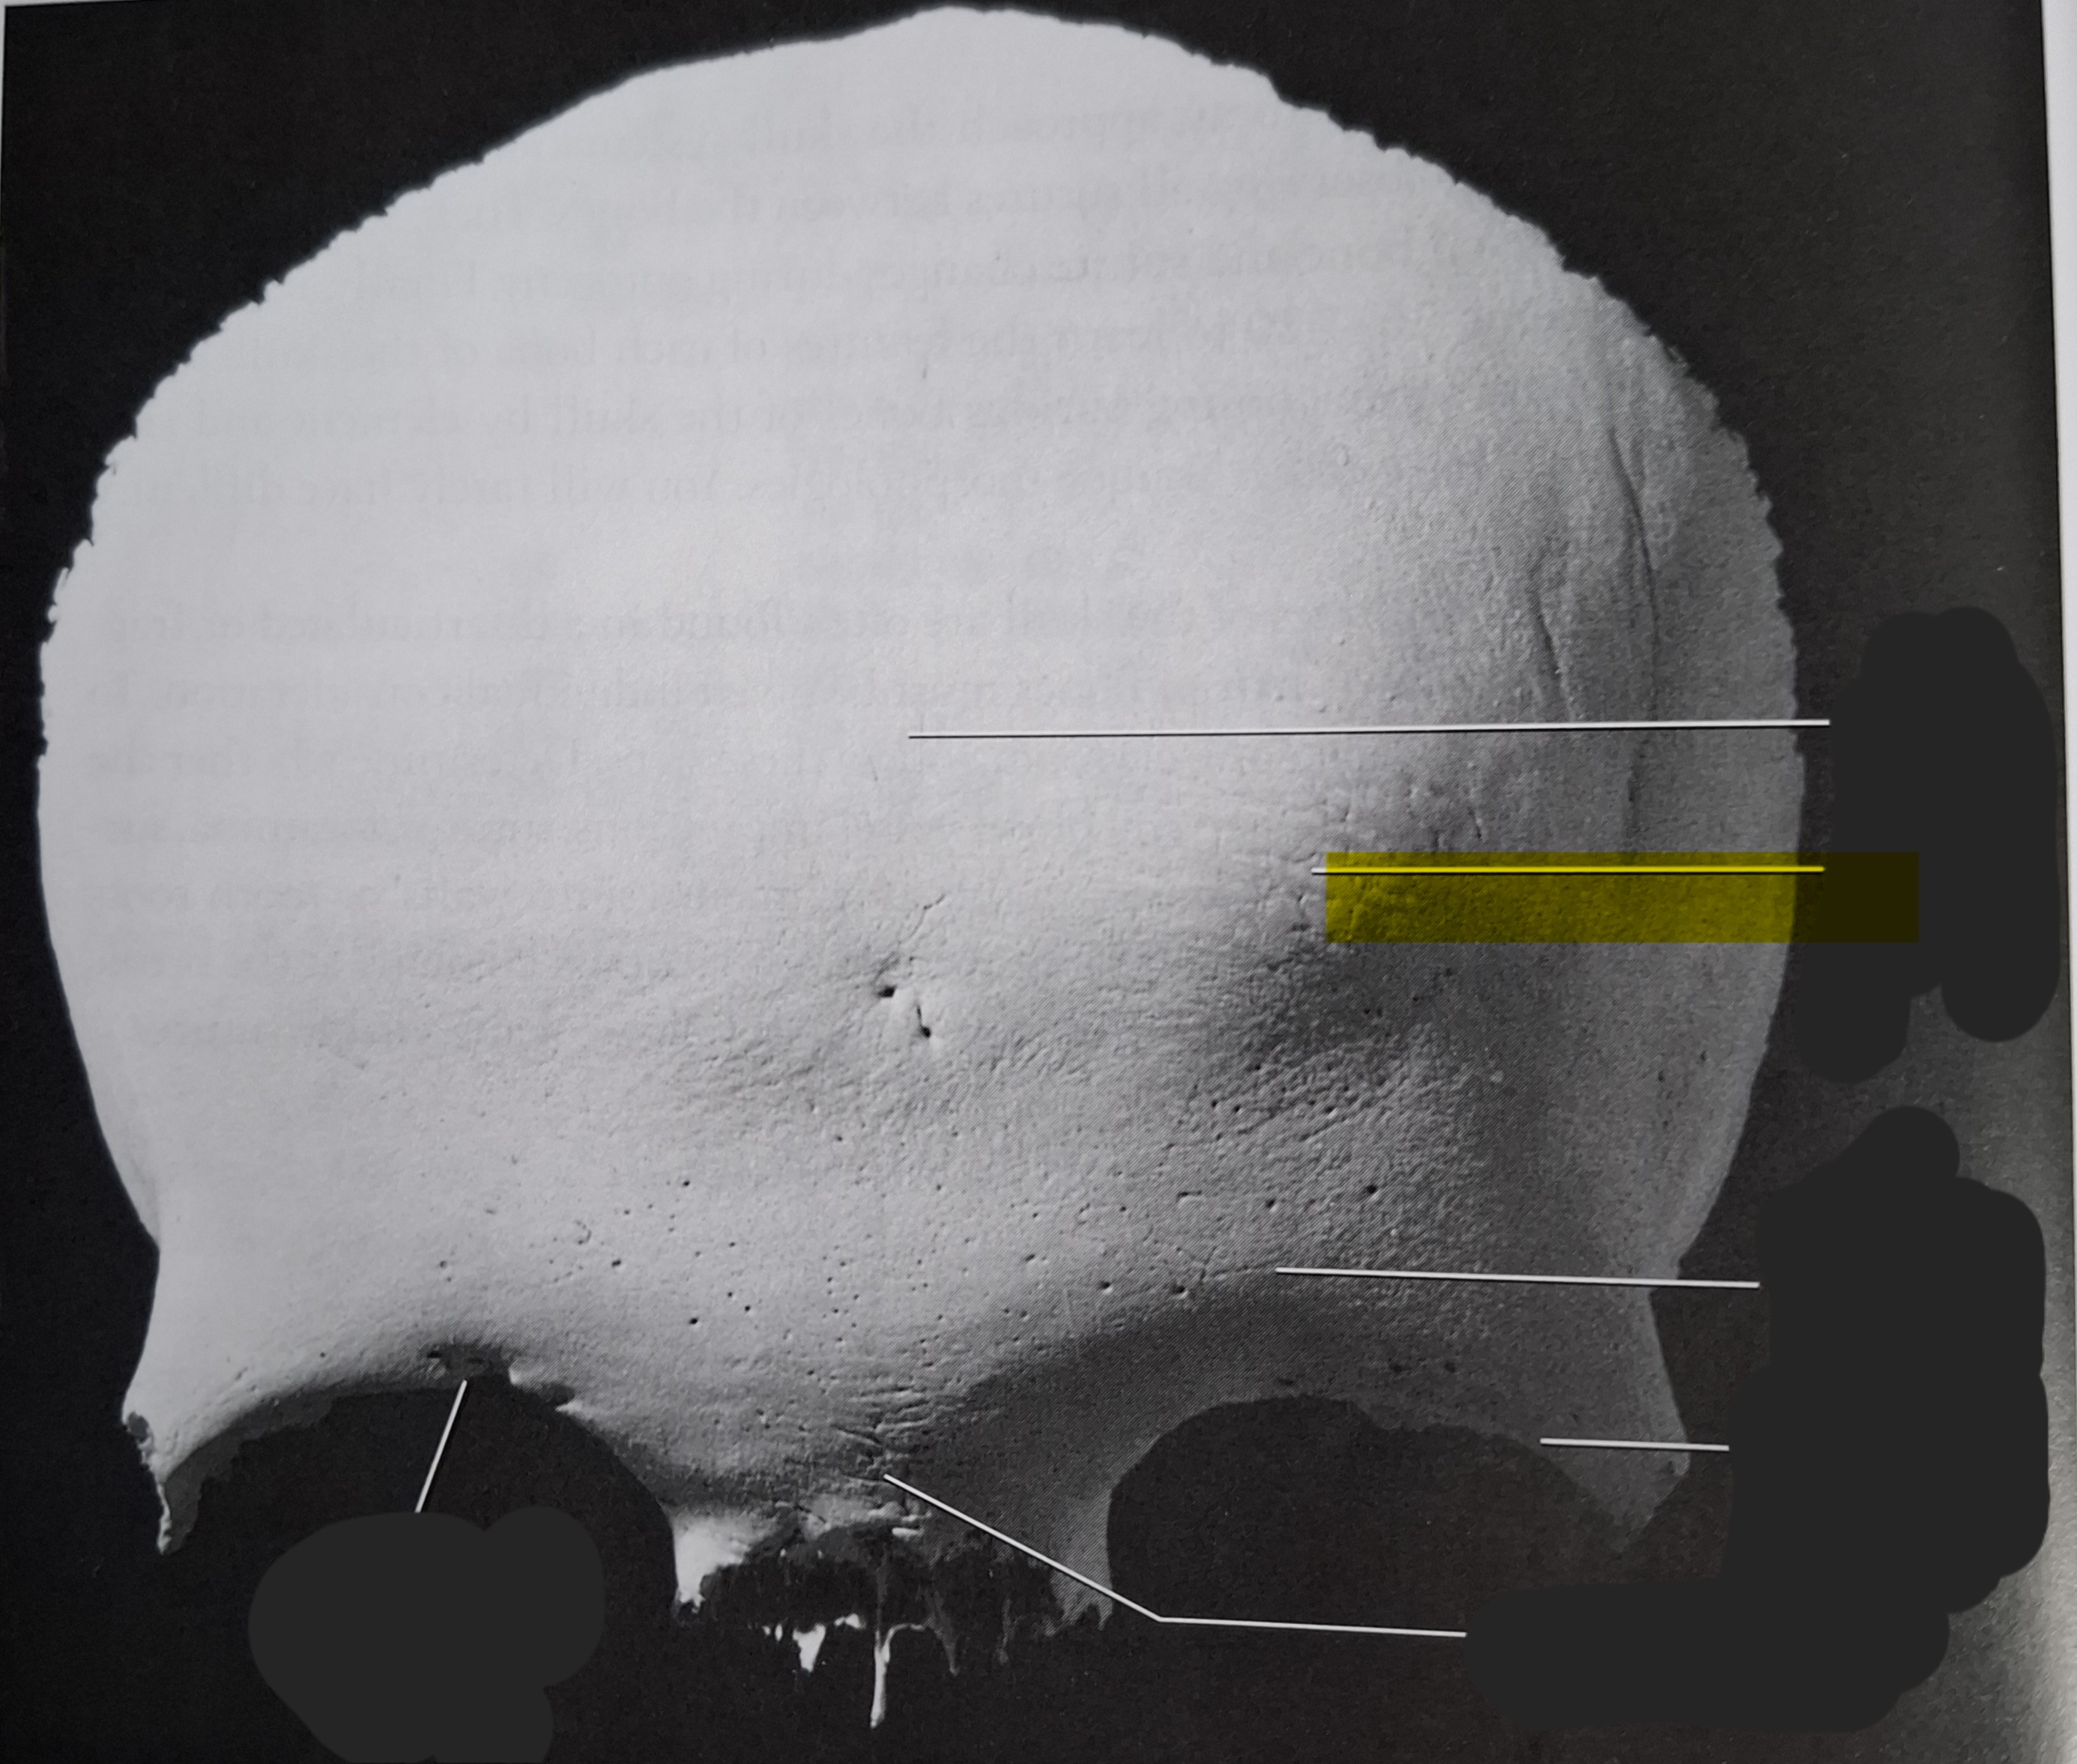

Occipital

Superior nuchal line

Inferior nuchal line

Foramen magnum

Occipital condyle

External occipital protuberance

Basilar part

Parietal

Superior temporal line

Inferior temporal line